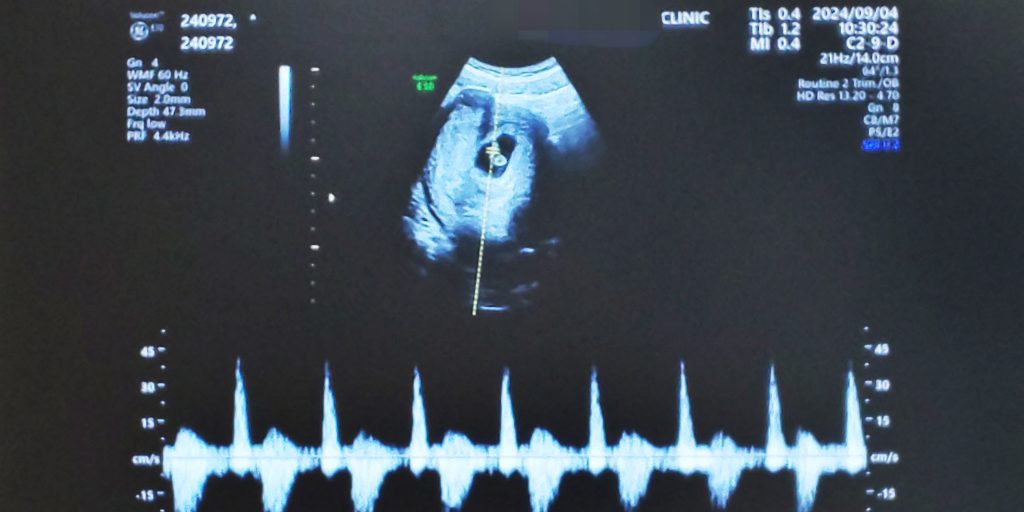

09/04 7w4d 全長0.9mm

始めての心拍確認!経過も順調とのこと。役所に妊娠届出書を提出し母子手帳を貰ってきました。妊娠している実感がイマイチなかったけど、マタニティーマークをバッグに着けたらようやく妊婦だと自覚することができました…